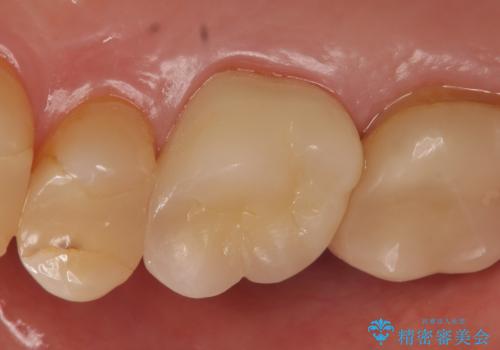

X線上で根尖病変を認めたため根管治療を行い、その後オールセラミッククラウンによる補綴を行いました

- オールセラミッククラウン…¥100,000、仮歯…¥10,000、ファイバーコア…¥20,000費用は治療当時の料金となります

オールセラミッククラウン(エコノミー)はスタンダード以上と違い、一塊となっているため欠けてしまうリスクが低いのが特徴です。

しかしその反面選択できる色の種類が少なく、色合いも単調であるという欠点もありますが、今回のケースのように前後の歯がクラウンの場合などでは十分に審美的な補綴が可能となります。